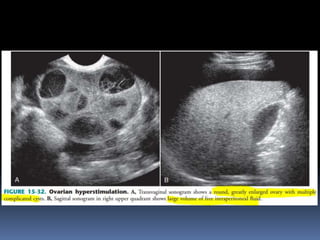

This document contains an image gallery from Dr. Mohit Goel showing various uterine anomalies and ovarian cysts. It includes images of an arcuate and unicornuate uterus, endometritis, a twisted ovarian pedicle, dermoid cysts of varying sizes and echogenicity containing hair, fat, and calcifications, and a combination dermoid cyst showing both mesh and plug structures. The gallery provides ultrasound images of different gynecological conditions for medical education and reference.